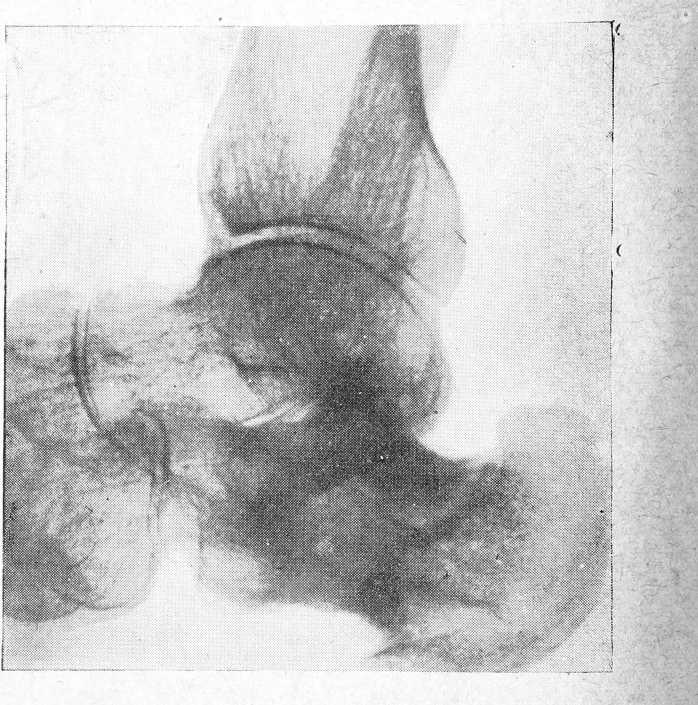

Рентгенограмма от 10 XII (рис. 1) указывает на резкий остеопороз всех костей голеностопного сустава, ясно выделяются на этом фоне лишь тонкие линии суставных поверхностей. Все суставные щели смазаны. Пяточная кость неправильной формы из-за наличия на верхней и нижней ее поверхностях значительных дефектов костной ткани. В средней части пяточной кости большой очаг разрежения, вокруг которого гомогенная уплотненная костная ткань. Верхний край имеет бахромчатый рисунок, задний и нижний края дифференцируются недостаточно четко. Слой мягких тканей смазан и утолщен.

Рис. 1.

С 9/XII начались перевязки с антивирусом Мазура. 100% антивирус вливался в рану, затем вводился туда влажный тампон; поверх тампона на рану и измененную кожу накладывалась марля, смоченная антивирусом. Такие перевязки производились через день.

Рентгенограмма от 28/III (рис. 2) (через 3 месяца 18 дней после начала лечения антивирусом) обнаруживает вполне четкий рисунок костей голеностопного сустава. Все эти кости имеют ясное структурное строение. Суставные щели определяются хорошо. Пяточная кость деформирована за счет дефекта на верхней ее поверхности. Края дефекта совершенно четкие, гладкие. На нижней поверхности имеется костный выступ (по типу „шпоры").

Рис. 2.

Вся пяточная кость имеет структурное строение с некоторым склерозом в средней ее части. Тени мягких тканей уклонений от нормы не представляют.

При осмотре б-ной 29/ V еще обнаруживается небольшой узкий ход в раневую полость (рис. 3). Болей при пальпации нет. Может ступать на пятку. Дома ходит без костылей. Рентгенограмма, сделанная 25 V, показала дальнейшие репаративные изменения в костях стопы.

Рис. 3.

Последний раз больная осмотрена 15 XI. Рана закрылась. Кожа совершенно нормальная. Конфигурация стопы не изменена. Болей при пальпации нет. Ходит хорошо без костылей и палки. Рентгенограмма от 15 XI (рис. 4) показывает хорошее структурное строение всех костей стопы. Суставные щели дифференцируются хорошо. Дефект пяточной кости (в верхней ее части) уменьшился. На нижней поверхности "шпора“. В средней части пяточной кости склероз.